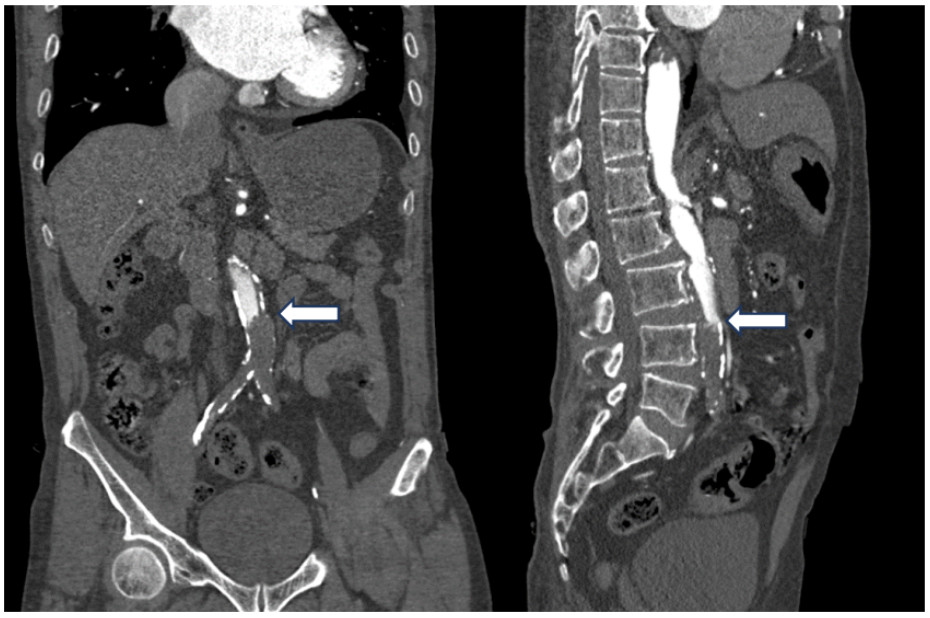

腹主动脉CTA成像示:腹主动脉近末端处-双侧髂总动脉-双髂外动脉、右髂内动脉、左髂内动脉起始部未见对比剂充盈,考虑腹主动脉急性闭塞(见图 4)。

| 注:A为冠状位,B为矢状位;腹主动脉远端未见对比剂充盈(箭头处) 图 4 患者主动脉CTA血管成像 |